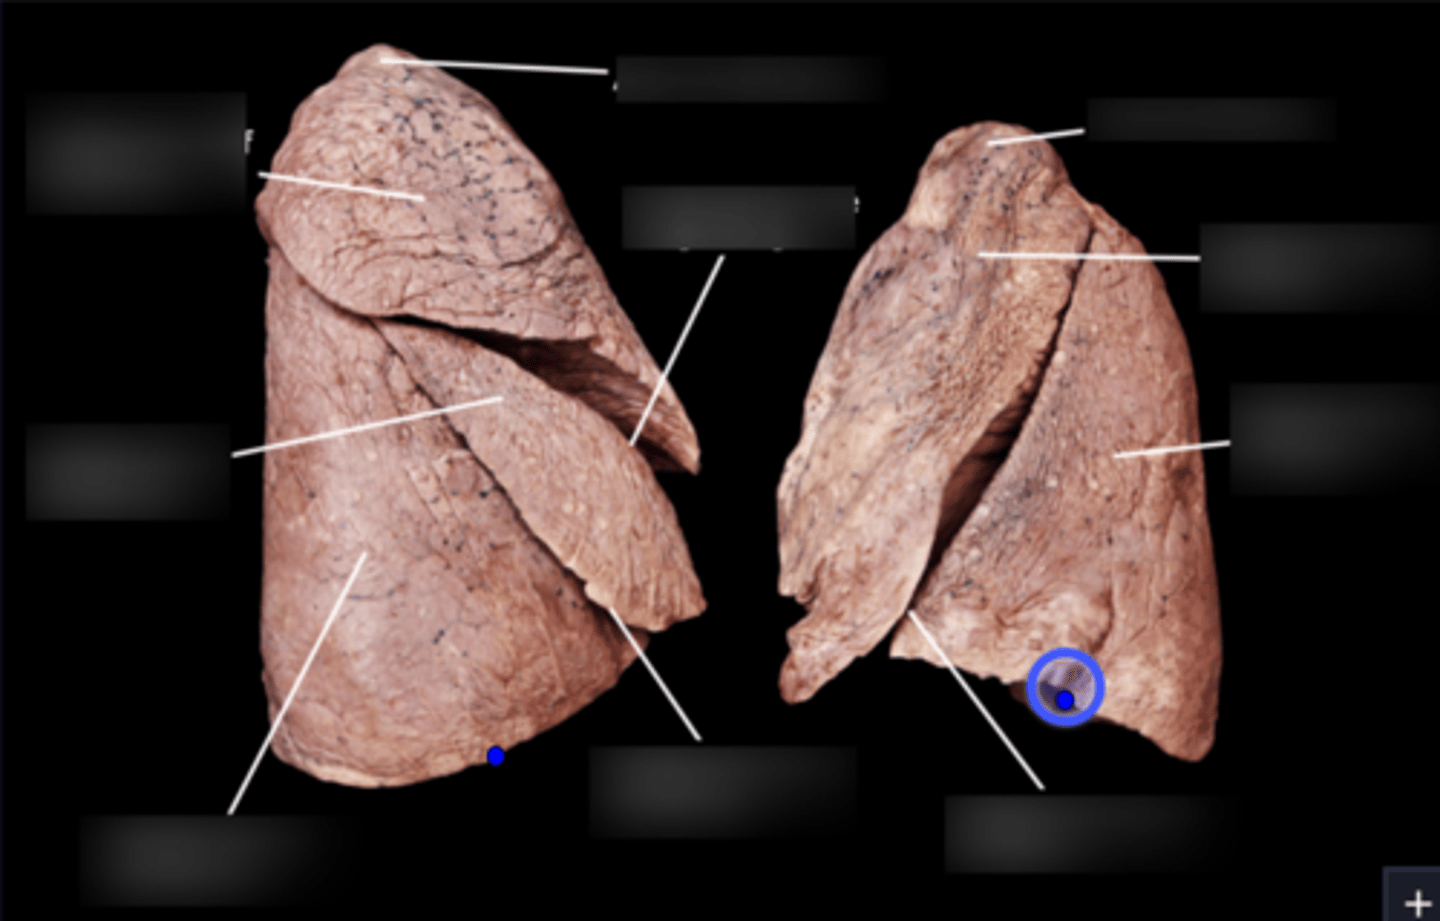

Superior lobe of right lung

Middle lobe of right lung

Inferior lobe of right lung

Superior lobe of left lung

Inferior lobe of left lung

Lingula

Apex

Base/Diaphragmatic Surface

Costal Surface

Mediastinal Surface

Anterior Margin

Posterior Margin